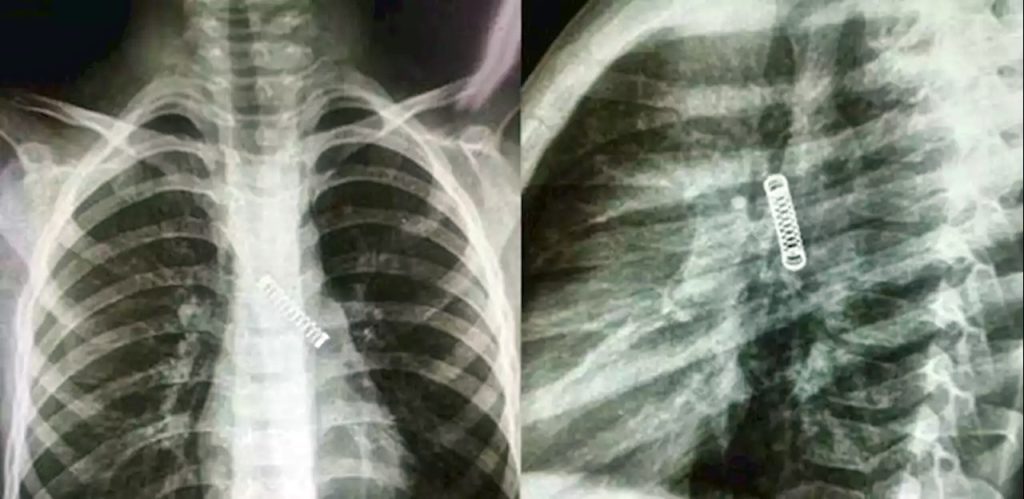

O menino foi submetido a um raio-X e os médicos ficaram surpresos ao encontrar um objeto de metal em seu pulmão esquerdo.

Um menino de 5 anos teve uma mola de metal removida de seu pulmão, depois do objeto ficar preso lá por três meses. O paraguaio de cinco anos sofria de uma tosse constante.